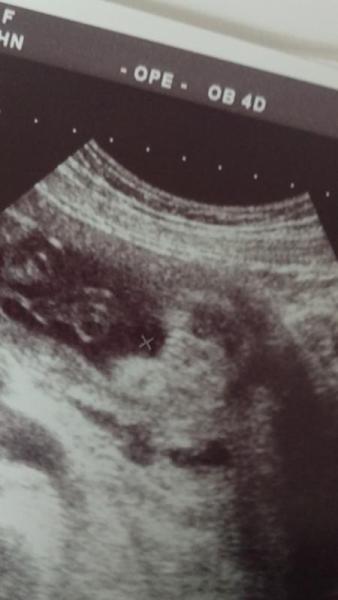

Hi, Der eine Arzt sagt Junge der andere Mädchen. Hoffe ihr könnt mir da weiter helfen. Lg Manu

Bild zu Junge oder Mädchen, was sagt ihr? - Schwanger - wer noch? Rund um die Schwangerschaft

würde jetzt auch mädchen sagen, aber ich denke es ist besser du wartest bis ein arzt es dir eindeutig sagen kann

wie weit bist du jetzt ? finde man kann so grad 3 striche erkennen, und daher sagen: Mädchen!

Ich würde eher auf Mädchen tippen. Zumindest sahen meine Jungs anders aus. Aber es ist auch etwas unscharf. LG

Huhu Ich würde auch auf Mädchen tippen :)